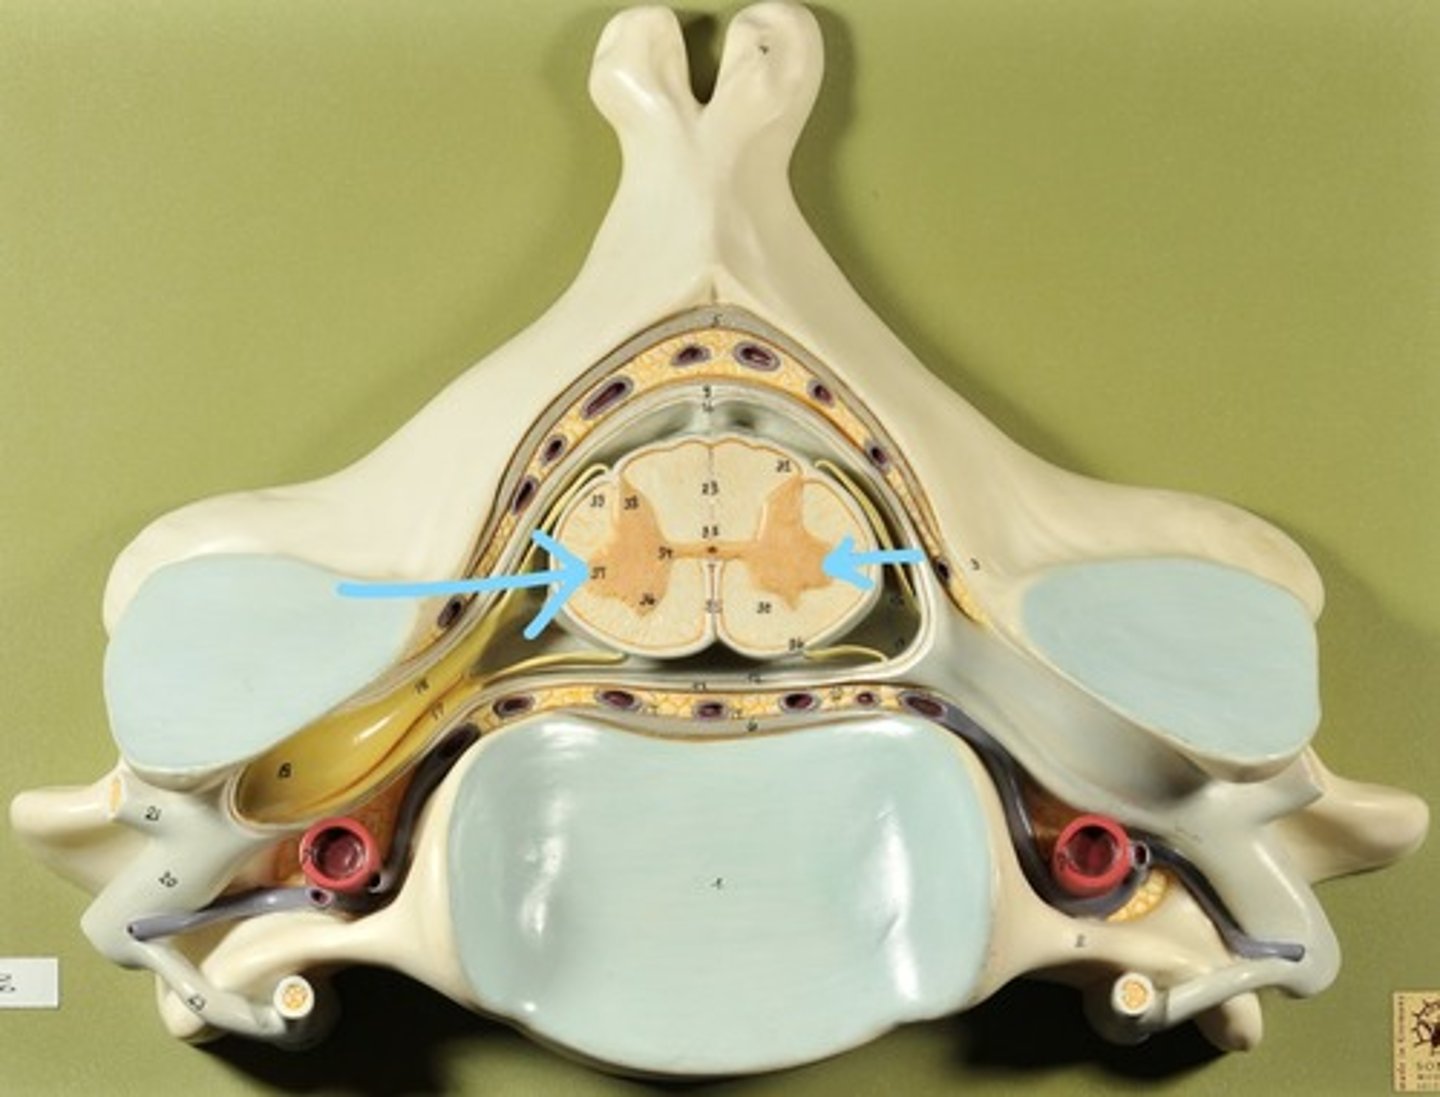

Identify all structures of spinal cord

White Matter of spinal cord

gray matter of spinal cord

Ventral Horns (gray matter)

Lateral Horns (gray matter)

Dorsal horns (gray matter)

Anterior Columns (white matter)

Lateral Columns (white matter)

Posterior Column (white matter)

central canal of spinal cord

Identify all structures

Pia Mater

Subarachnoid Space

Arachnoid mater

Subdural Space (brown line)

Dura mater

Epidural Space

Dorsal Root Ganglion

Dorsal Root

Ventral Root

Spinal Nerve